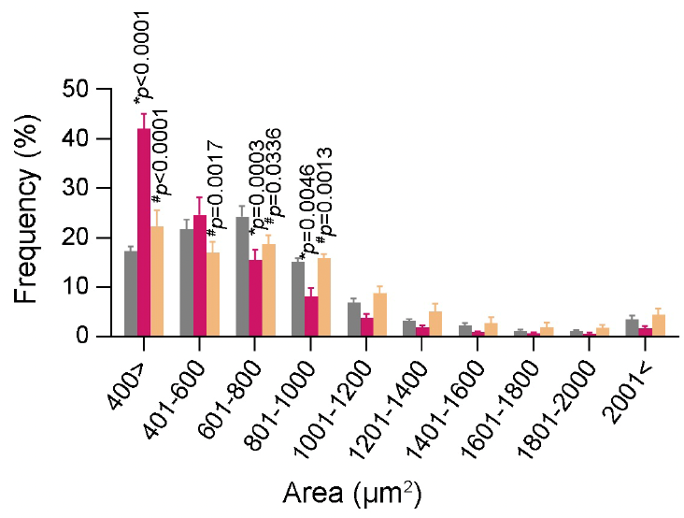

뇌-말초조직 네트워크 규명을 위한 신경회로 발굴 및 제어연구

- 연구주제 : 근육-뇌 신경회로 역할 규명을 통한 인지기능 및 근감소증 제어연구

- 연구주제 : 뇌혈관장애-유래 인지기능 저하 및 근감소증 제어기전 연구